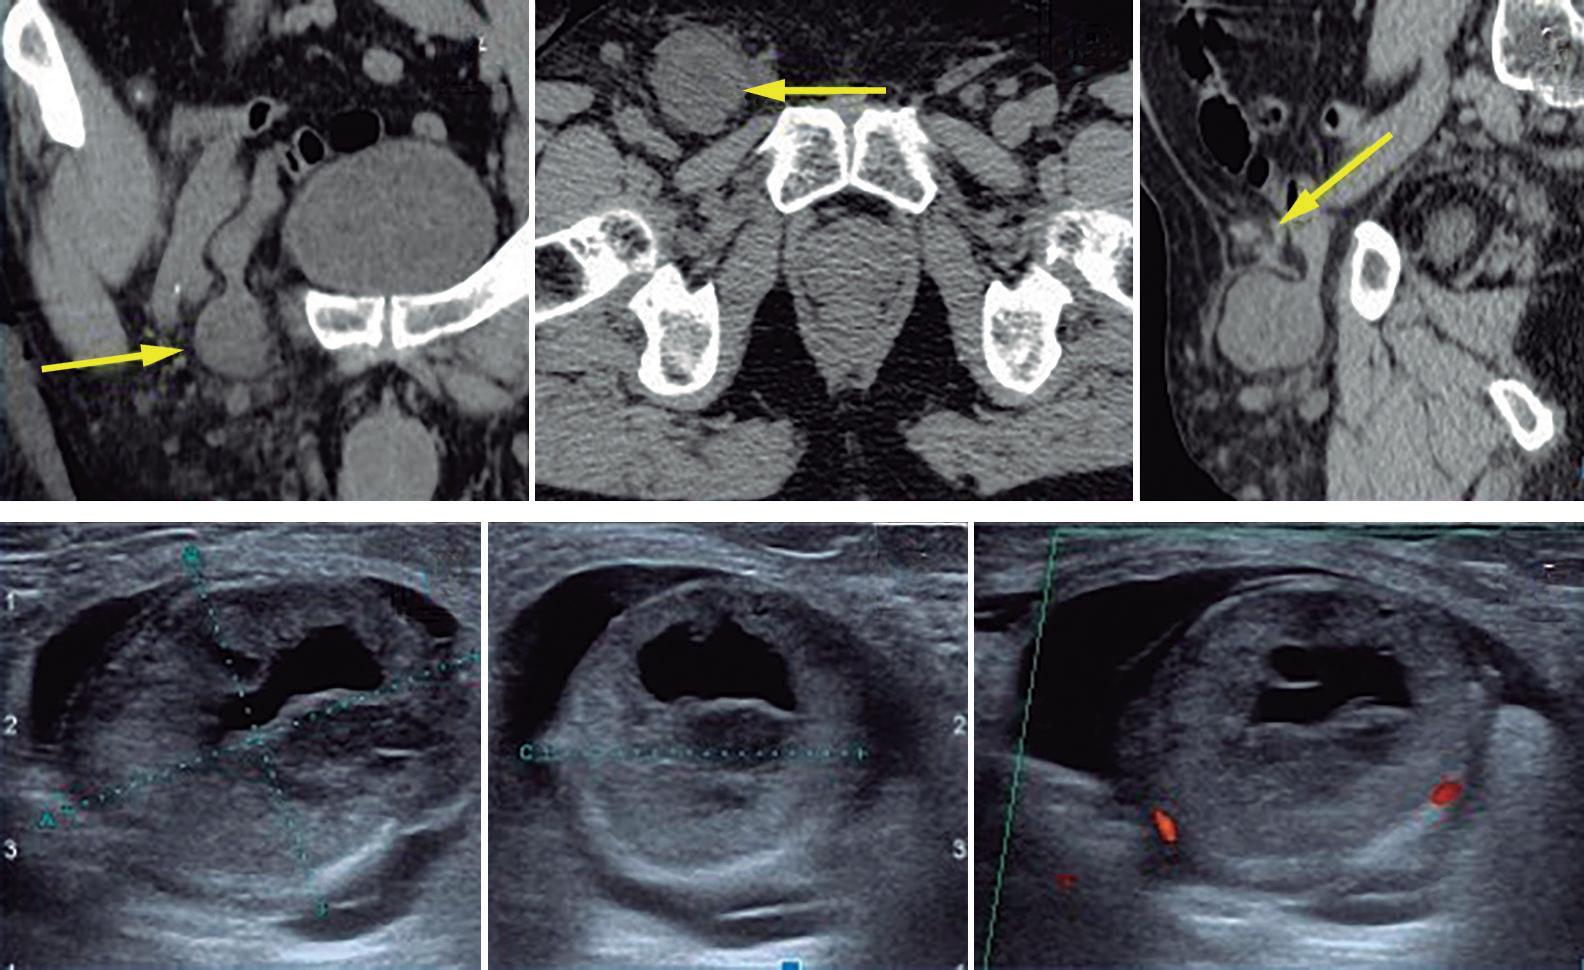

Obstrucción intestinal duodenal en una adolescente femenina

Duodenal Bowel Obstruction in a Teenage Female Patient